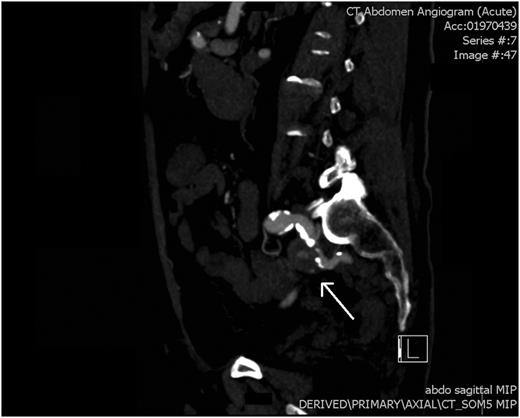

An arterial phase CT abdomen with IV contrast was performed. This revealed a contrast blush within the descending colon closely associated with an aneurysm of the internal iliac artery. The possibility of an arterial fistula to the colon was raised, and a vascular surgery consult was sought. Angiography confirmed a false aneurysm arising from the proximal aspect of the left internal iliac artery along its medial and inferior wall. Endovascular coil embolization was performed with occlusion of the vessel at the level of the aneurysm.

CT angiogram: a saggital view showing pseudoaneurysm of the left internal iliac artery (white arrow).